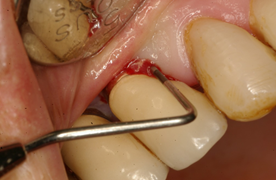

In brief, from the debate held at the peri-implantitis workshop of the First International Congress of Implantology of the School of Dentistry, Universidad de la República, we can conclude that: 1) surgical treatment must always be preceded by non-surgical treatment based on mechanical debridement and the use of antiseptics such as 0.12% chlorhexidine, with a waiting period of three months before starting the surgical treatment (Figs. 8, 9).

Surgical treatment involves: a) opening a mucoperiosteal flap and removing the granulation tissue; b) treating the surface of the implant either with gauze with saline, gauze with 0.2% chlorhexidine, gauze with 3% H2O2, local antibiotics on the implant surface, sodium bicarbonate or glycine spray, Er: YAG laser, mechanical curettage or implantoplasty; c) regenerative or resection techniques; d) systemic antibiotics (amoxicillin 500 mg and metronidazole 500 mg for seven days); e) application of 0.12% chlorhexidine until mechanical hygiene is resumed; f) supportive therapy for three to six months.